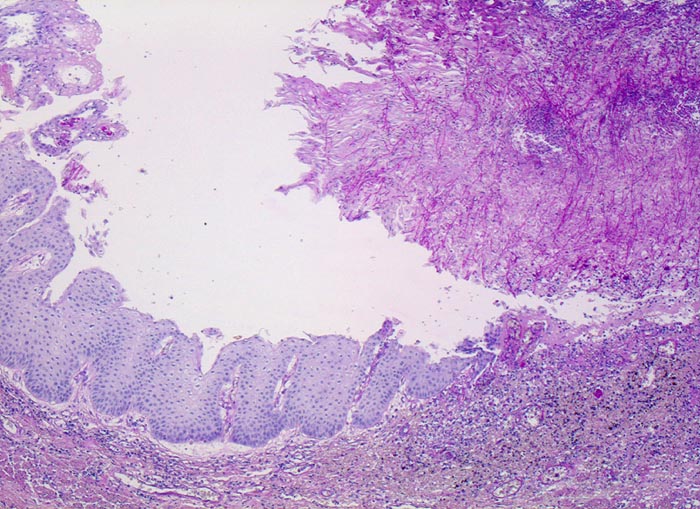

Die Schleimhaut links im Bild ist weitgehend unauffällig. Am rechten Bildrand ist ein Ulkus erkennbar, welches von einem dicken Geflecht aus Pseudohyphen bedeckt wird.

Weisse, streifenförmige Beläge auf der Mucosa

Mann, 75 Jahre, mit bekanntem multiplen Myelom. Autopisepräparat. Progrediente Dysphagie.